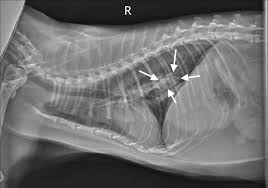

Lung Tumors Lap Of Love from www.lapoflove.com Cancer can be detected early by observing certain signs and symptoms. While most cat owners have already initiated cancer treatment by the time lung cancer is diagnosed, the persistent, hacking cough usually alerts cat owners to the possibility that it may be infiltrating the lungs. A tumor site located in the lung tissue or subpleural: But most cats will display one or more of the following very few mammary gland growths in cats are benign—85 to 90 percent are malignant and spread to lymph nodes, lungs and the chest cavity. Difficulty in breathing can be a sign, because some cancers can cause fluid in the lungs. When a person has lung cancer, they have abnormal cells that cluster together to form a tumor. Feline lung cancer is divided into 2 categories: In many cases, cancers will grow over quite a long period of time, and initially there may just be vague signs of surgery is the single most common form of therapy for cancer and is the treatment most likely to result in a cure.

If your cat shows any signs of weight loss, eating a. Lung cancer signs & symptoms. The above subtypes are the most common, but when your lung cancer tumor is looked at under a microscope, it might reveal even more specific information. Lung cancer is a cancer that starts in the lungs. Learn more about the symptoms, diagnosis and treatment of lung cancer in cats here. Cancer in cats is unfortunately considered relatively common and more prevalent than ever before. Common symptoms of lung cancer in pets are coughing, exercise intolerance, and other respiratory signs that may be present from several weeks to what are the treatment options for lung tumors in cats and dogs? Primary lung tumor in cats signs of cancer in cats are similar to other diseases. It is caused by uncontrolled cell growth, and affects a wide range of cell types and organs in the body. Metastatic lung disease is more common than primary lung tumors in cats. While most cat owners have already initiated cancer treatment by the time lung cancer is diagnosed, the persistent, hacking cough usually alerts cat owners to the possibility that it may be infiltrating the lungs. Cancer is a disease that occurs due to the uninhibited division of abnormal cells. Cat breast cancer, most often referred to as feline mammary cancer, can be fairly obvious except that some cats do not readily let an owner feel or look at your veterinarian can find early warning signs of cancer in cats from a good history and physical exam, long before you would notice anything at.